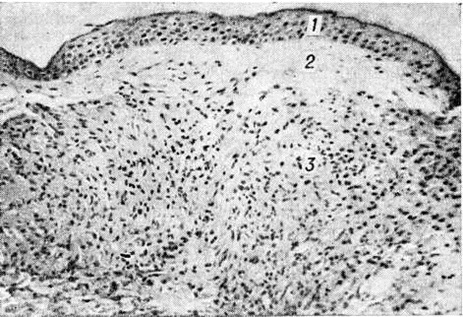

Гистологический исследование биопсийного материала имеет важное значение для установления диагноза и прогноза болезни. Биопсии подвергаются участки поражённой кожи, изредка — поверхностно расположенные нервы. Морфологически изменения при Лепра проявляются в виде гранулем двух полярных типов — лепроматозного (LL) и туберкулоидного (ТТ), а также трёх групп — погранично-туберкулоидной (ВТ), пограничной (ВВ) и погранично-лепроматозной (BL).

Гистологически лепроматозный тип характеризуется лепроматозной гранулемой кожи, которая представляет инфильтрат, расположенный в сетчатом слое, отделённый от эпидермиса непоражённой зоной коллагеновой ткани. Основными клеточными элементами лепроматозной гранулемы являются лепрозные клетки; кроме того, наблюдаются отдельные плазматические, лимфоидные клетки, единичные фибробласты, многоядерные пенистые клетки (цветной рисунок 1—6). Лепрозные клетки относятся к макрофагам, характеризуются бледным ядром и «пенистой» цитоплазмой (рисунок 5) за счёт содержания липидов. Лепрозный макрофаг на ранних стадиях содержит жирные кислоты, фосфолипиды, ненасыщенные липиды; на стадии развития процесса преобладают нейтральные жиры и кислотные липиды. Большинство исследователей считает, что основная масса липидов представляет собой продукт метаболизма и распада микобактерий Лепра. Наиболее характерная особенность лепрозного макрофага — нахождение и размножение в нем большого количества микобактерий Лепра, то есть явление незавершённого фагоцитоза (смотри полный свод знаний). В цитоплазме лепрозной клетки выявляется высокий уровень окислительно-восстановительных ферментов, кислой фосфатазы, неспецифической эстеразы и не обнаруживается активность липазы. Для гистологический картины LL характерно также наличие капилляров со значительным сужением их просвета за счёт пролиферации и набухания эндотелиальных клеток, содержащих большое количество микобактерий типа «глоби». Кожные нервы пронизаны инфильтратами из микробосодержащих клеток (цветной рисунок 7 и 10). Микобактерии обнаруживаются также в клетках эндоневрия. В лепроматозных поражениях большой давности отмечается частичное или полное разрушение придатков кожи (фолликулов волос, сальных и потовых желёз).

При туберкулоидном типе патологический процесса сформировавшийся инфильтрат может быть массивным, занимающим все слои собственно кожи, или располагаться отдельными очагами. Характерно разрушение субэпидермального слоя коллагеновой ткани с расположением гранулемы непосредственно под эпидермисом с эрозированием последнего. Основную массу гранулемы составляют эпителиоидные клетки (смотри полный свод знаний), расположенные в центре и окружённые по периферии валом из лимфоидных клеток (смотри полный свод знаний Лимфоциты), встречаются гигантские многоядерные клетки типа Лангханса (смотри полный свод знаний Гигантские клетки), в небольшом количестве обнаруживаются плазматические клетки (смотри полный свод знаний), тучные клетки (смотри полный свод знаний), фибробласты. В период обострения в гранулеме наблюдается обилие полиморфно-ядерных лейкоцитов (смотри полный свод знаний). Клеточные элементы не содержат микобактерий и липидов. Характерно утолщение нервных стволов за счёт массивной инфильтрации эпителиоидными клетками.

Морфологически структуры, содержащие элементы, характерные для обоих типов Лепра и являющиеся как бы переходной стадией между полярными типами, характерны для пограничной Лепра При недифференцированной Лепра наблюдается картина банального хронический воспаления (смотри полный свод знаний) без специфических изменений. Основными гистологический критериями, определяющими принадлежность к классификационным группам Ридли — Джоплинга, являются следующие морфологический особенности инфильтрата. 1. Клеточный состав гранулемы. В верхней половине спектра (ТТ, ВТ и ВВ) характерно наличие эпителиоидных клеток (цветной рисунок 8) и для ТТ — многоядерных (гигантских) клеток типа Лангханса (цветной рисунок 9). При ВВ эпителиоидные клетки часто отделены друг от друга отёком. В нижней части спектра (BL и LL) эпителиоидные клетки уступают место макрофагам, цитоплазма которых по мере приближения к типу LL становится более плотной, пенистой и содержит жир. 2. Плотность популяций микобактерий. Количество микобактерий возрастает пропорционально от верхней части спектра к нижней. В числовом выражении показатель бактериальной насыщенности лепроматозного инфильтрата для ТТ, ВТ, ВВ, BL и LL составляет 0/1; 0/2,5; 3/4,5; 4/5,5; 5/6,5 соответственно. 3. Количество и топография лимфоцитов в гранулеме. Для ТТ и ВТ свойственно высокое содержание лимфоцитов, расположенных в виде плотного бордюра вокруг массы эпителиоидных клеток. При ВВ и LL количество лимфоцитов чаще снижено, они рассеяны по гранулеме и не образуют вала. 4. Поражение кожных нервов. Для туберкулоидной части спектра характерно значительное утолщение нерва за счёт массивного инфильтрата (повышение максимального диаметра пучка при ТТ). Для ВВ и BL патогномоничны изменения периневрия в виде луковичной кожуры (onion skin) за счёт расслоения его инфильтратом из лимфоцитов, плазмоцитов (при В В) или бактериосодержащих макрофагов (при BL). 5. Отношение к эпидермису. При ТТ и ВТ гранулема располагается непосредственно под эпидермисом и может эрозировать его. При ВВ, BL и LL между инфильтратом и эпидермисом постоянно остаётся непоражённая зона толщиной 30 — 75 микрометров — так называемый слой Ипа, состоящий из коллагеновой ткани.